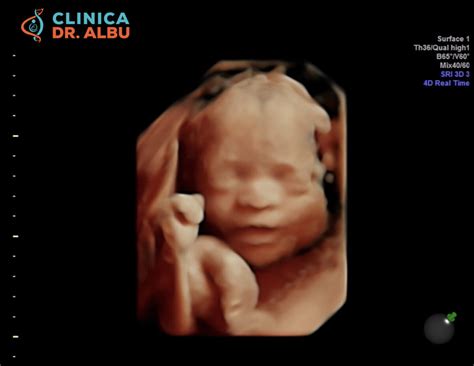

Morfologia fetală de trimestru II se realizează, în general, între săptămânile 20 și 24 de sarcină, ideal în săptămâna 22. Aceasta permite o examinare mult mai detaliată a structurilor fetale, inclusiv a feței, toracelui, diafragmei, abdomenului, membrelor și coloanei vertebrale. Ecografia permite observarea în timp real a mișcărilor fetale și realizarea de reconstrucții 3D și 4D. De asemenea, se pot vizualiza cordonul ombilical și placenta pentru a descoperi eventuale complicații.